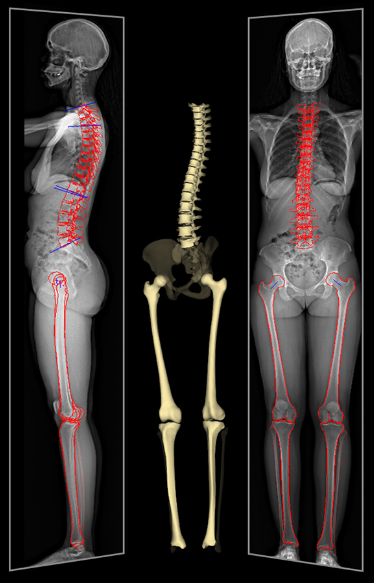

L'une des caractéristiques les plus remarquables de la cabine EOS est sa capacité à produire des images tridimensionnelles du squelette de haute qualité, en position debout. Cette visualisation avancée permet aux médecins d'analyser avec précision les structures osseuses et les articulations et leurs différents angles, offrant ainsi une compréhension plus complète des morphologies osseuses et des anomalies anatomiques.

La cabine EOS se distingue par sa capacité à produire des images d'une netteté et d'une précision exceptionnelles. Grâce à une technologie avancée de balayage, elle capture des images radiographiques haute résolution avec une exposition extrêmement faible aux rayons X, réduisant ainsi considérablement l'exposition aux radiations pour les patients et le personnel médical.